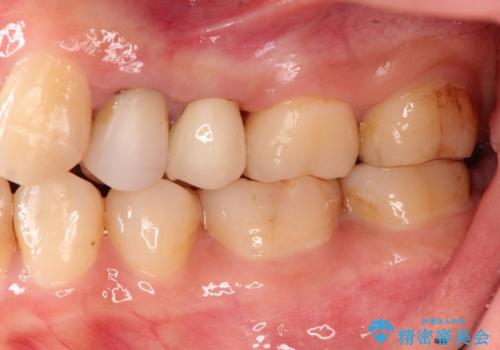

- 歯が欠けたとのことで来院されました。

過去に治療してあった左上の歯が一部欠けていました。

かぶせ物と詰めてある修復物を除去すると歯肉の中まで虫歯になっていました。

歯を部分矯正で引き上げて、虫歯を徹底的に取り除き、適合の良いかぶせ物を装着する計画としました。